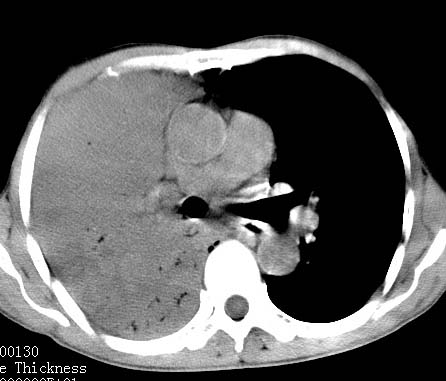

病人女 60岁 咳嗽 气促十余天,大叶性肺炎.

右肺上下叶均见 大片状密度增高影,边界清晰,其内可见支气管充气征,气管支气管通畅。纵膈略向右移位,其内无肿大淋巴结影。首先考虑炎性病变。不排除一些特异性的炎症。不知道发烧吗??wbc高吗??建议治疗后复查!!

看影响还是首先考虑炎性改变,建议实验室检查,还有要警惕炎性肺泡癌,具有的枯枝征象。